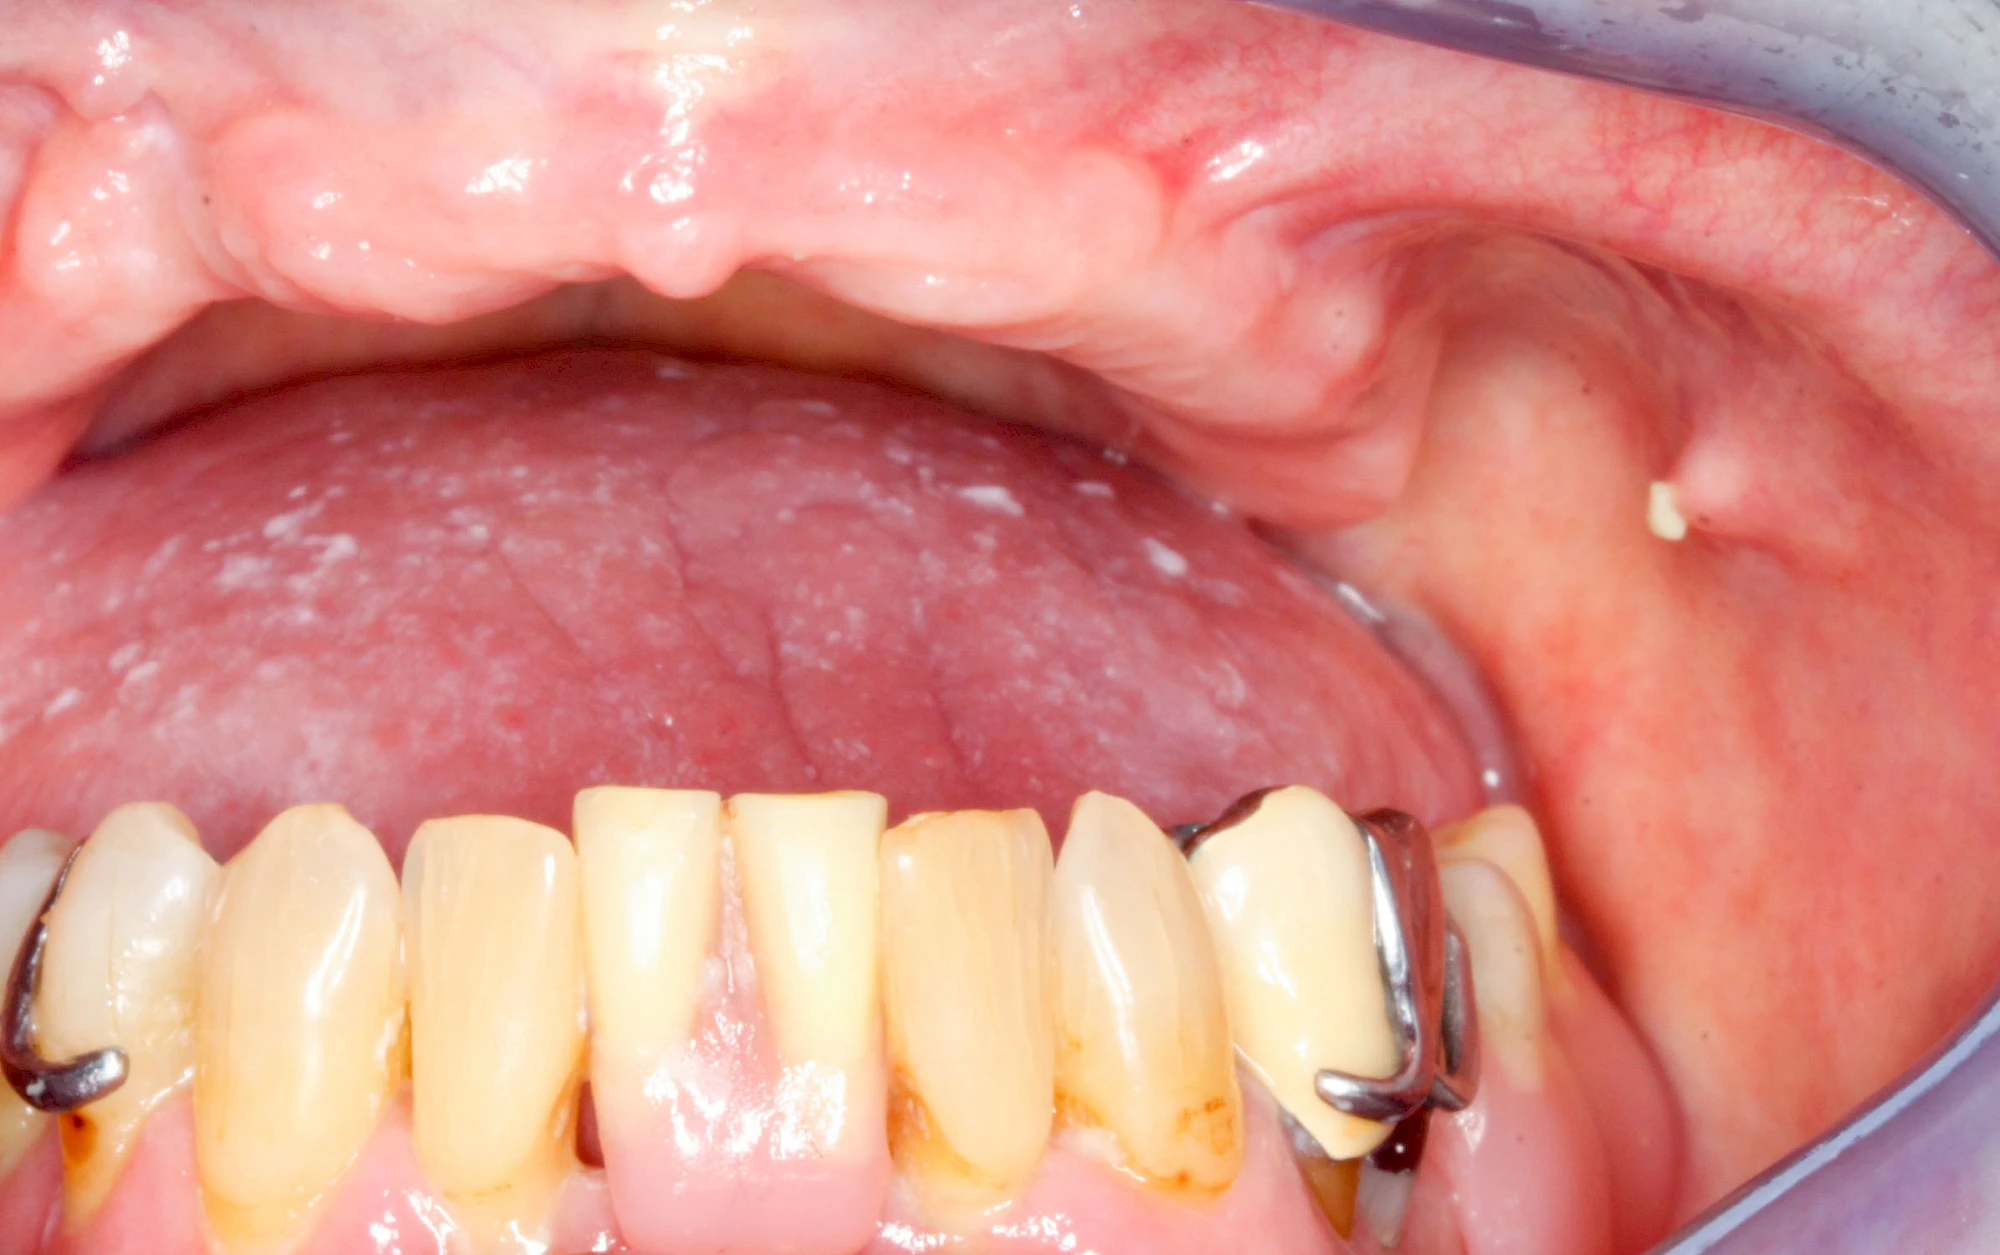

Speicheldrüsenzyste

Eine Speicheldrüsenzyste (Speicheldrüsenretentionszsyte) kann als Schwellung oder Auftreibung meist im Bereich der größeren Ausführungsgängen auffallen, wenn z. B. ein Speichelstein den Speichelfluss behindert. Vor allem bei den Mahlzeiten, wenn der Speichelfluss angeregt wird, nimmt die Auftreibung oder Schwellung schmerzhaft weiter zu. In der Regel ist die Unterkieferspeicheldrüse (Glandula sublinugalis) betroffen. Man spricht dann auch von einer Frosch- bzw. Fröschleingeschwulst (Ranula). Bringt sanftes Massieren der Schwellung bzw. Auftreibung keine Verbesserung, sollte ein Arzt oder Zahnarzt hinzugezogen werden